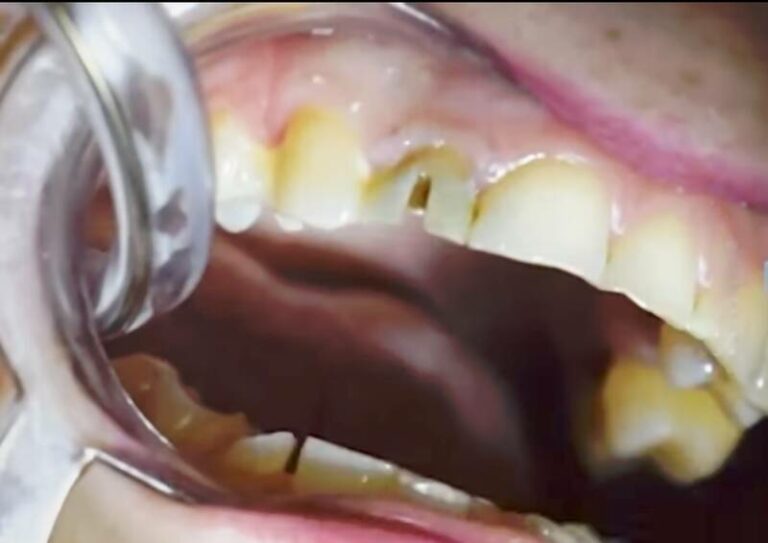

Crown Decay Picture Summit Dental Can You Put A Crown On A Broken Tooth This is a serious dental condition that. A dental crown surrounds the entire tooth, providing strength and protection from additional injury. If a large piece of tooth breaks off or the tooth has a lot of decay, the dentist may grind or file away part of. If your crown fell out and there is no tooth left in the mouth,. Can You Put A Crown On A Broken Tooth.